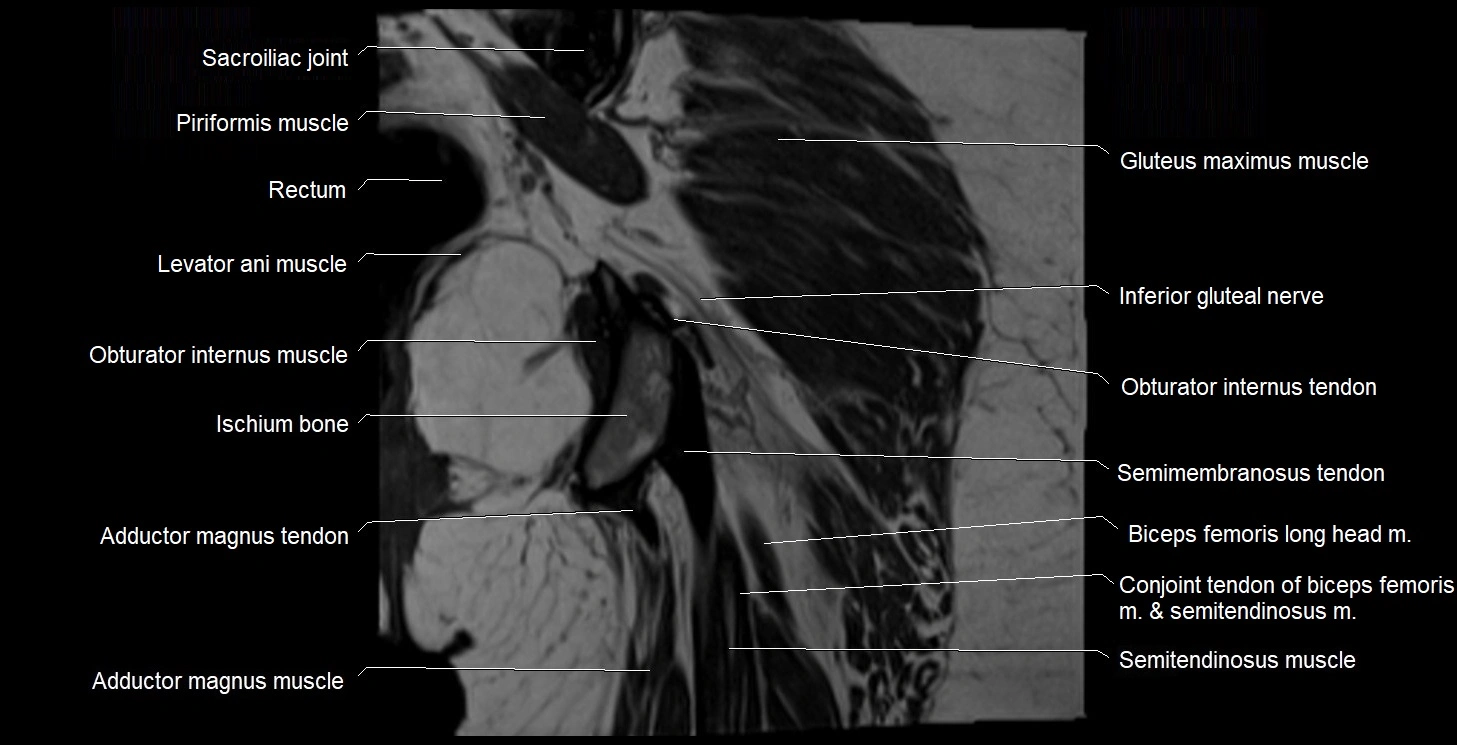

- Conjoint tendon of biceps femoris & semitendinosus

- Gluteus maximus muscle

- Iliococcygeus muscle

- Inferior gemellus muscle

- Ischiococcygeus muscle

- Ischium bone

- Levator ani muscle

- Obturator internus muscle

- Obturator internus tendon

- Rectum

- Sacroiliac joint

- Semimembranosus tendon (proximal)